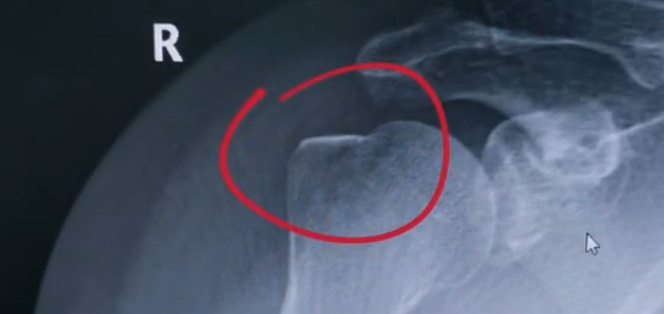

肩關(guān)節(jié)的X射線片子,看到?jīng)]有明顯的骨折,但是實(shí)際上已經(jīng)骨折了。那么是如何發(fā)現(xiàn)的呢?醫(yī)生對(duì)于做出疾病診斷的時(shí)候,會(huì)選擇什么樣的檢查方式。也更好的配合醫(yī)生,來(lái)解決問(wèn)題。1米高的地方摔了下來(lái),右側(cè)肩關(guān)節(jié)與地面相撞受傷了。當(dāng)時(shí)的胳膊還能活動(dòng),疼痛感很明顯,但是在家觀察了一天,這個(gè)腫脹沒(méi)有明顯的加重。然而問(wèn)題是什么呢?疼痛始終不能緩解,所以就需要到醫(yī)院檢查。醫(yī)生查看關(guān)節(jié)的受限也很明顯,尤其做外展這個(gè)動(dòng)作的時(shí)候,幾乎沒(méi)辦法自行完成。肩關(guān)節(jié)內(nèi)的這個(gè)韌帶和肌腱可能還沒(méi)有發(fā)生嚴(yán)重的損傷。

首先做一個(gè)普通的X光檢查,看一看有沒(méi)有大的骨折或大的問(wèn)題。結(jié)果是沒(méi)有發(fā)現(xiàn)太嚴(yán)重骨折損傷問(wèn)題。結(jié)合病史,還是有點(diǎn)疑惑。因?yàn)樘鄣奶珔柡?。x光檢查和他的疼痛之間不匹配,患者沒(méi)有骨頭的損傷,疼痛不至于達(dá)到這么嚴(yán)重的一個(gè)程度。是否有一種情況掩蓋住了病情。這也是X線檢查的通病。x光檢查它是一個(gè)二維的檢查,有可能患者肩關(guān)節(jié)啊發(fā)生了骨折。但是它的位置被前方或者側(cè)方的這個(gè)骨頭遮擋住了。不是立體的就沒(méi)辦法看到后方的情況。想要更加進(jìn)一步的明確問(wèn)題,判斷是否有骨頭的損害怎么辦?

進(jìn)一步就是查CT,可以更全面的角度去判斷問(wèn)題的所在。就會(huì)發(fā)現(xiàn)是否骨折可以看到確實(shí)存在著骨折,還好骨折不算嚴(yán)重??梢哉f(shuō)是一個(gè)骨裂。這個(gè)肩關(guān)節(jié)與地面撞擊的時(shí)候,暴力沒(méi)有達(dá)到那么強(qiáng)。讓骨頭整個(gè)發(fā)生一個(gè)巨大的斷裂,而是造成了一個(gè)小的劈裂。適當(dāng)?shù)倪M(jìn)行一些抗炎止痛藥的使用。適當(dāng)?shù)倪M(jìn)行一些消腫治療,患者癥狀也就消失了。